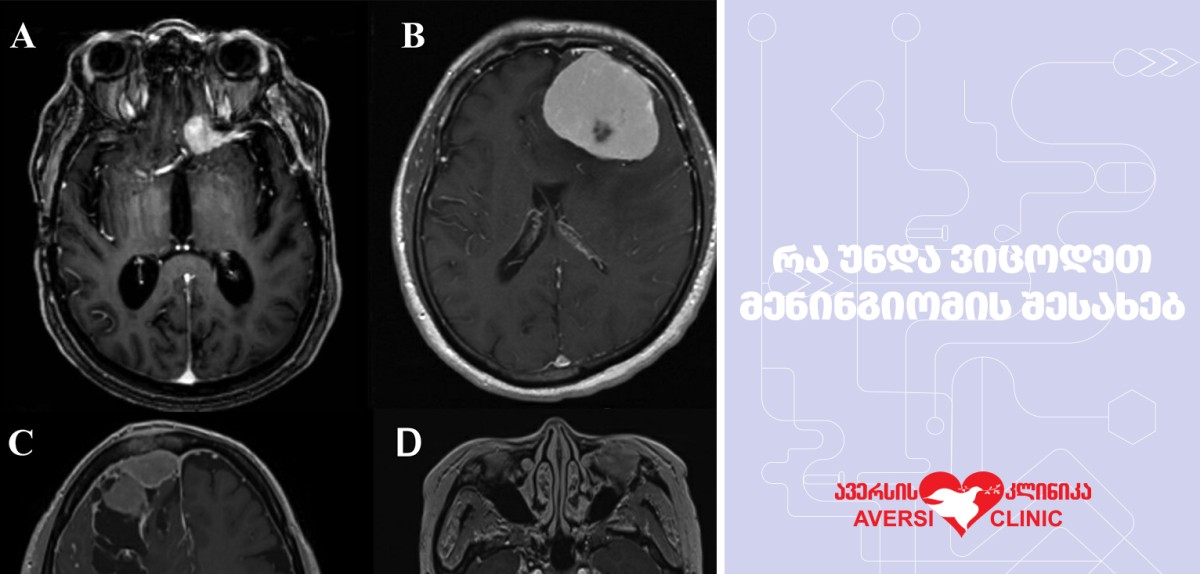

როგორ მიმდინარეობს მენინგიომის დიაგნოსტიკა?

დიაგნოსტირება ხდება თავის ტვინის კომპიუტერული ტომოგრაფიის ან მაგნიტურ-რეზონანსული ტომოგრაფიის საშუალებით.